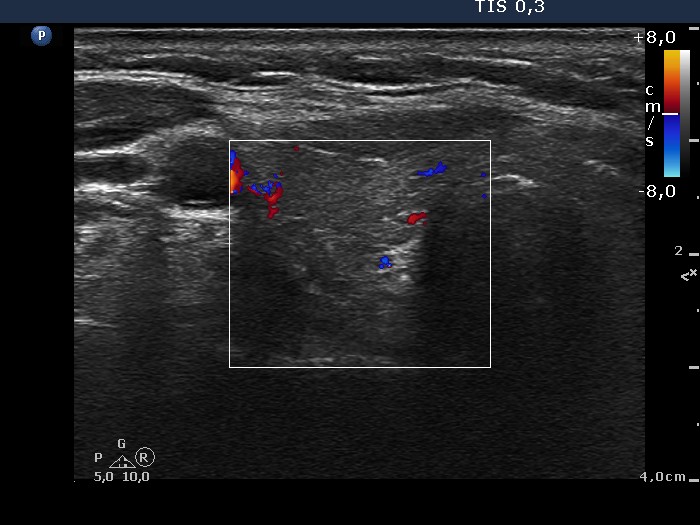

Ultrasonography. The thyroid was moderately hypoechogenic. There was a hypoechogenic nodule presenting hyperechogenic figures in the ventral part of the left lobe. The lesion had irregular, partly lobulated, partly blurred borders and presented intranodular blood flow.

Cytology resulted in Hürthle-cell tumor. Considering the ultrasound pattern, we raised the possibility of an oxyphilic variant of a papillary carcinoma.

- It is equivocal how to categorize the intranodular hyperechogenic figures in this case. They partly correspond to proliferation of connective tissue because the video proves the synchronous presence of similarly bright lines and granules within the lesion. The issue is the coexistence with microcalcification.

- The tumor presents partly blurred, partly lobulated margins and is suspicious having invasive borders.